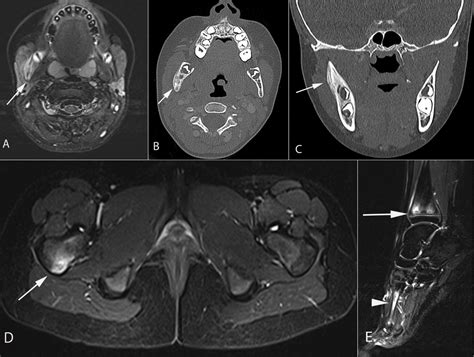

Diagnostic Approach and Imaging

Diagnosing Chronic Multifocal Osteomyelitis is a process of exclusion. Because there is no single laboratory blood test that confirms the diagnosis, physicians rely on a combination of clinical findings, imaging, and, in some cases, a bone biopsy to rule out other more serious conditions like malignancy or bacterial osteomyelitis.

MRI (Whole Body) The gold standard for identifying multifocal lesions without radiation exposure.

X-rays Useful for evaluating bone damage, though often normal in the early stages.

💡 Note: A whole-body MRI is highly recommended by specialists to identify asymptomatic lesions that might otherwise go undetected.